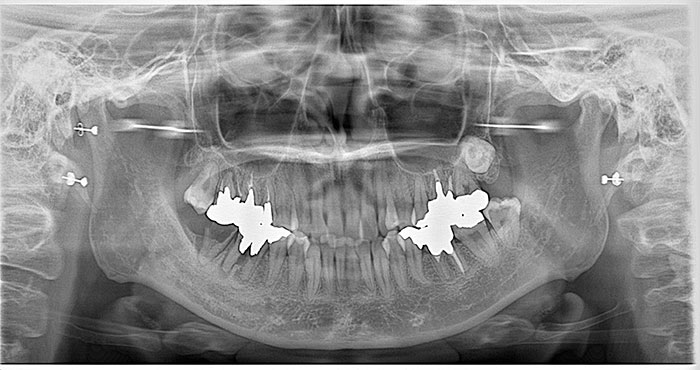

骨造成とインプラント

Before

After

下顎の骨量が乏しいため骨造成をし、その後インプラント治療を行いました。

かみ合わせも良好でしっかりと機能しています。